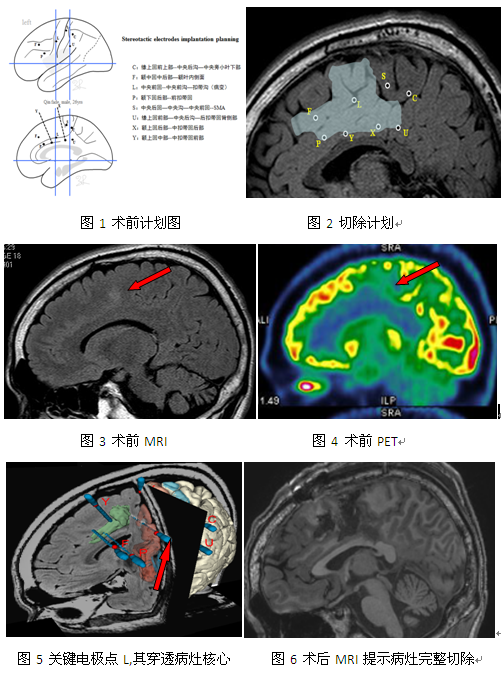

癫痫中心对患者进行了详细的术前评估,仔细阅读患者头颅磁共振发现左侧扣带沟及额叶内侧面有异常信号,类似皮质发育不良,但病变的边界不清,很难确定切除范围。经过仔细讨论后,建议行颅内电极植入术明确致痫灶范围,电极植入后抓捕患者多次发作,视频脑电图主要表现为:先兆(右肩部电流感)→面肌,颈肌,右上肢强直,其中进入病灶核心的L电极放电明显(L1-3,Y3-4,X6-7,X12-13,P1-3→L6-7),而脑代谢检查显示:左额前、中扣带回、内侧面低代谢。经过癫痫中心讨论后决定,致癎灶位于额叶内侧面(包括扣带回和辅助运动区),随即为其确定了治疗方案,在神经导航的基础上,清楚的辨别皮质发育不良和关键电极点,唤醒下切除致痫灶,术后恢复顺利,此后再无癫痫发作。

额叶癫痫是癫痫疾病中最常见的一种类型,可分为内侧额叶癫痫和外侧额叶癫痫。内侧额叶包括不同的运动区,多以运动性发作为主要表现,发作时间较短,多见于夜间发作,强直性或运动性姿势较为突出,很快引起继发性全身发作。由于位于大脑内侧面,距大脑表面较远,且与颞叶、边缘系统有广泛的纤维联系),这些功能性的网络存在使得癫痫可以在额叶内外播散阻碍EEG的准确定位,人们也很难通过癫痫发作的临床表现来确定症状起始区。而SEEG可以多角度、深入脑深部灰质探测异常放电,尤其对于大脑内侧面的检查极为便捷,经过该患者病变核心的L电极1-7点放电极为明显,第7点以后没有放电,我们将此L7作为病灶切除的外侧界,为外科医生的手术切除指明了方向,此病例也深刻的体现了SEEG技术在癫痫领域的独特优势。